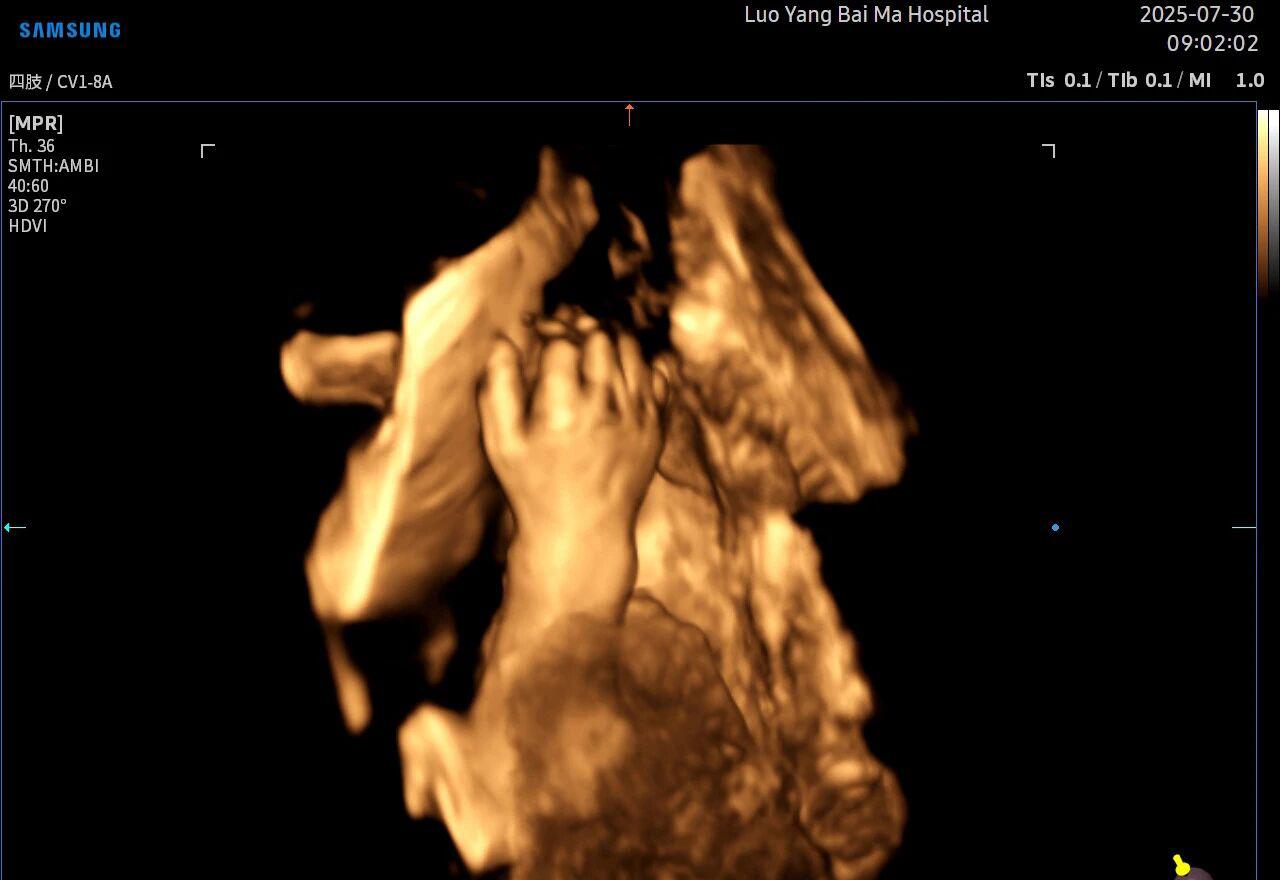

5D智能彩超拥有更高的分辨率和更强的图像处理能力,能够呈现出接近“IMAX电影画质”的细腻影像 。它采用一种被称为“水晶成像”的技术,能够穿透组织,将胎儿的骨骼、器官和组织结构以极其清晰、立体的形态展示出来。这种高清晰度对于观察胎儿微小的解剖结构细节至关重要,例如手指、脚趾、耳廓形态等,有助于医生发现一些在传统超声下不易察觉的细微异常,为排畸诊断提供了更丰富的视觉信息。

2. 全方位、多角度的“360度”观察

传统超声检查有时会因为胎儿体位、羊水量等因素的限制,导致某些部位观察不清。5D智能彩超技术能够实现对目标结构进行360°全方位、多切面的自由旋转观察。医生可以像“雕塑家”一样,从任意角度审视胎儿的解剖结构,尤其对于形态复杂的心脏、颅脑和脊柱等部位,这种能力可以极大弥补单一平面的局限性,帮助医生更全面地评估其发育状况。

4. 温情互动,一次充满感动的“亲子会面”

除了严谨的医学诊断价值,5D彩超也为准爸妈们带来了无与伦比的情感体验。通过高清逼真的动态影像,您可以清晰地看到宝宝的每一个细微表情和动作,仿佛他(她)就在眼前。这份提前到来的“亲密接触”,不仅能极大地缓解孕期的焦虑,更能加深家庭成员与未出世宝宝之间的情感连接,让等待的每一天都充满更具体的幸福感。